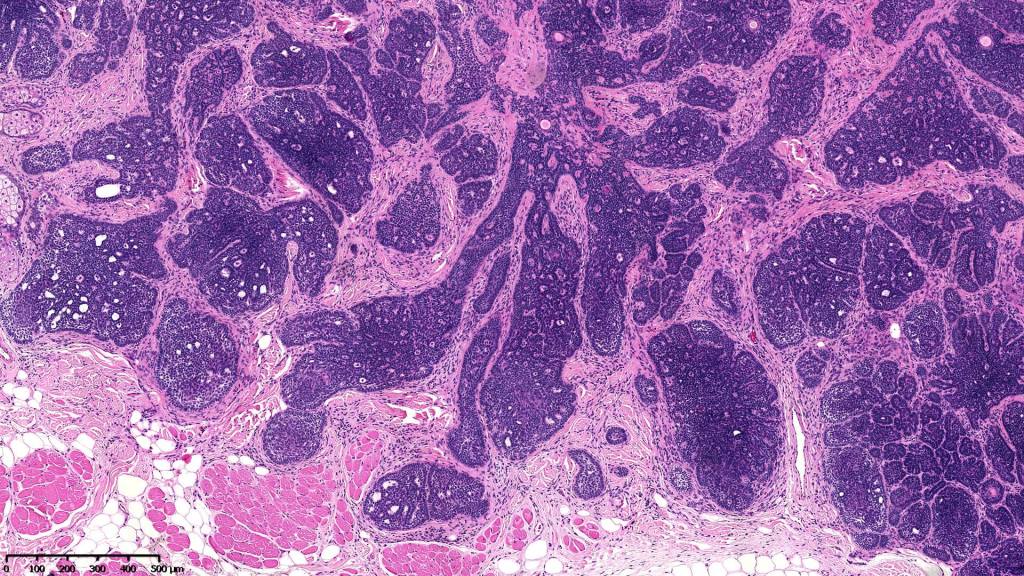

•Sharply circumscribed, unencapsulated nodule in deep dermis +/- subcutaneous fat or deeper (trichoepithelioma is much more superficial)

•Variably sized but generally large, basophilic tumor nodules composed of small uniform basaloid cells with minimal cytoplasm

•Peripheral palisading but no retraction artifact or stromal mucin deposition

•A rich fibromyxoid mesenchymal stroma with variable papillary mesenchymal bodies (sometimes these are absent)